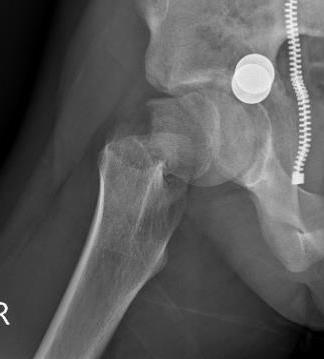

Delbert Classification

Type 1

- transepiphyseal separation / fracture

- rarest

- associated with hip dislocation

- AVN 100%

Type 2

- transcervical fracture

- commonest 50%

- AVN 50%

Type 3

- basicervical

- second most common 30%

- AVN 30%

Type 4

- intertrochanteric fracture

- AVN 10%